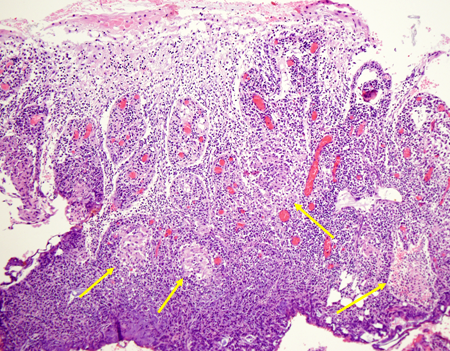

M. giunge alla nostra attenzione, all'et� di 7 anni, per la prima volta al cospetto del nostro allergologo: il suo problema infatti � quel gonfiore �rosso� a carico della labbra e gengive (soprattutto superiori), che interessa anche le guance, il mento e la regione peri-orbitale. Il collega descrive il quadro come una vera e propria ipertrofia da �infiltrazione� (edematosa ed eritematosa) delle gengive e delle labbra, che appaiono fissurate (mai cheilite), con cute arrossata e discheratosica al volto. Trattasi di granulomatosi orofacciale quadro clinico confermato anche dalla biopsia orale.

I genitori raccontano che le hanno gi� tentate tutte (terapia antibiotiche, antimicotiche, anti-infiammatorie) senza ottenere alcun beneficio. L'allergologo allora chiede se la manifestazione appaia correlata all'ingestione di qualche alimento e la madre riferisce che �s�, dottore, sembra esserci una correlazione con il latte, sa M. � un grande bevitore di latte (presenta RAST per latte e uovo positivi), ma l'associazione vale solo per l'edema, mentre l'ipertrofia sembra assolutamente indipendente, perch� persiste nonostante l'alimento non venga assunto�. Il ragazzo non presenta alcun altro segno e sintomo associato: non perdita di peso (anzi � in soprappeso), non febbre, non disturbi gastrointestinali di alcun genere. Gli accertamenti ematochimici mostrano un emocromo nella norma, negativit� degli indici di flogosi (VES 6 e PCR negativa) e delle IgG (1257), ASCA e ANCA negativi, non deficit del C1q esterasi inibitore, negative Mantoux e coprocolture, calcemia e ACE sierica nella norma, normali le sottopopolazioni linfocitarie. Vengono eseguiti anche test di funzionalit� intestinale al doppio zucchero (lattulosio/ramnosio) che dimostra un aumento patologico della permeabilit� alle macromolecole (rapporto L/M 0.049 v.n. <0.026) e il dosaggio della calprotectina fecale (indicatore altamente sensibile di flogosi intestinale) che risulta invece assente. Considerata la possibile associazione tra morbo di Crohn e granulomatosi oro-facciale viene eseguita una gastroscopia, una colonscopia con biopsie e una ileoscopia con videocapsula che mostrano un quadro di duodenite cronica di grado lieve, con una mucosa duodenale con aspetti di iperplasia follicolare linfoide (soprattutto dell'ileo terminale e valvola ileo-ciecale) e una colite afosa ad impronta eosinofila. Pertanto, l'aumento della permeabilit� intestinale associata all'esito dell'esame istologico orientano fortemente verso una genesi allergica della granulamatosi orofacciale e quindi avviamo una dieta di esclusione per latte, uovo e derivati. A un mese dall'avvio della dieta il quadro appare notevolmente migliorato, seppur la risposta alla dieta sia in realt� parziale: scomparsa dell'edema labiale e gengivale, persistenza invece dell'infiltrato duro e parenchimatoso al labbro superiore e gengiva, anche se ridotto. Sempre nella norma l'emocromo e negativi gli indici di flogosi. Il miglioramento clinico, nonostante l'assenza di segni di allergia, la presenza di prick e RAST test negativi, ci impone di insistere sulla necessit� di continuare la dieta di esclusione. Tuttavia l'adesione del ragazzo alla dieta non � molto rigorosa: si hanno infatti 2 episodi di riacutizzazione dell'edema labiale in seguito all'ingestione di uova, con presenza di moderata ipereosinofilia periferica (eosinofili 470/mm3) a conferma delle trasgressioni dietetiche (con necessit� di utilizzare steroide a brevi perioidi, con peraltro efficacia). A un anno dalla diagnosi, la dieta di esclusione non aveva portato ad alcun miglioramento clinico, anzi nonostante un'adesione rigorosa (questa volta!), si era assistito a un franco peggioramento: labbra edematose, fissurate, la mucosa gengivale tumefatta, che impedivano al ragazzino perfino di sorridere. Cute perianale arrossata, con piccola ulcera interglutea. All'emocromo persisteva un' eosinofilia periferica, ma era presenta anche lieve anemia (Hb 11 g/dl con MCV 76), ipoferritinemia (10.85), ulteriore aumento della permeabilit� al test al doppio zucchero (0.079) e positivizzazione della calprotectina fecale (58 mg/kg), lieve aumento della VES (32), positivizzazione dei c-ANCA e negativi apparivano i patch-test per gli allergeni maggiormente implicati nella granulomatosi oro-facciale (cannella e sodiobenzoato). Questi nuovi reperti ci imponevano quindi di rivalutare completamente la malattia anche dal punto di vista endoscopico e istologico. In corrispondenza del retto, sigma e colon discendente erano presenti papule rilevate ulcerate al centro e piccole afte diffuse, a livello ileale distale la mucosa appariva granulare ma senza lesioni ulcero-erosive. Il risultato istologico delle biopsie coliche dimostrava la presenza di infiltrato cronico transmucoso con presenza di granulomi, quadro compatibile con il morbo di Crohn.